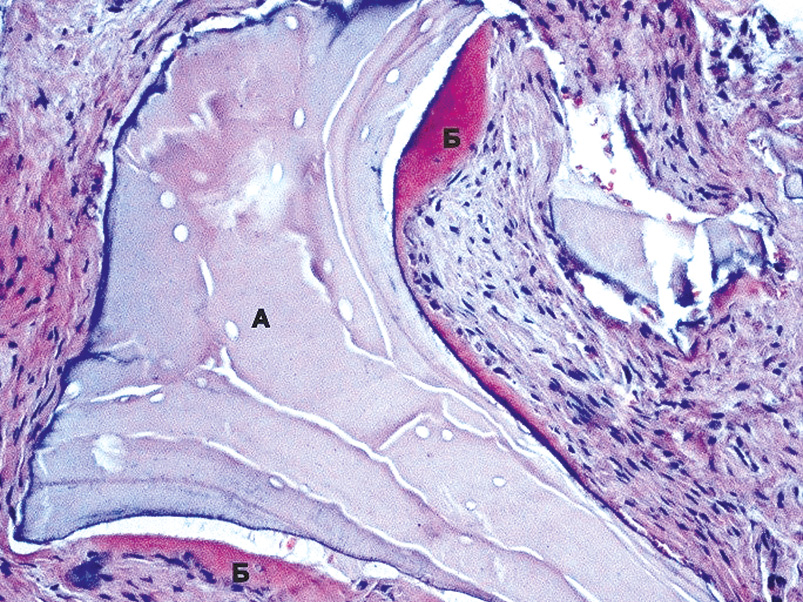

На поверхности трансплантированного гранулированного костнопластического материала определяли остеобласты. В соединительнотканной строме на границе с костнопластическим материалом отмечается образование остеоида (рис. 7).

Рис. 7. Фрагмент новообразованной костной ткани через 120 дней после трансплантации. Образование остеоида (Б) в соединительнотканной строме на границе с костно-пластическим материалом (А). Окраска гематоксилин-эозин. ×150.

Fig. 7. Fragment of newly formed bone tissue 120 days after transplantation. Osteoid formation (B) in the connective tissue stroma at the border with the bone graft (A). Hematoxylin-eosin stain, ×150.